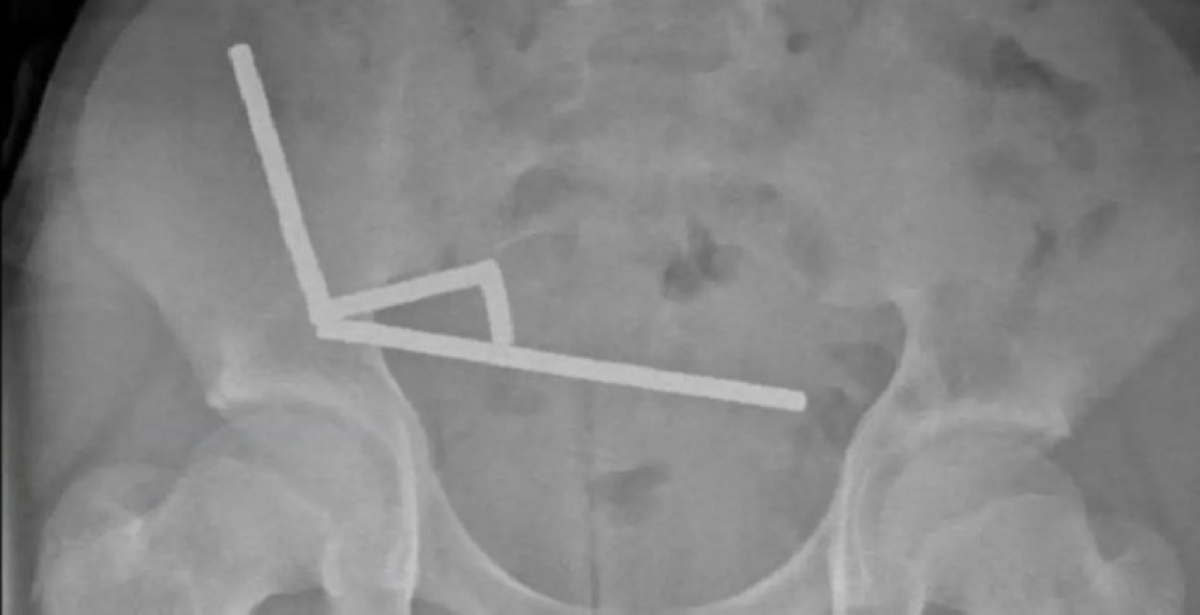

وبحسب تقرير لموقع ScienceAlert، فإن الصبي نُقل إلى مستشفى «تاورانغا» وهو يعاني من آلام شديدة في البطن، ليكتشف الأطباء لاحقًا وجود مئات المغناطيسات المعدنية التي التصقت ببعضها داخل الأمعاء، مسببة انسدادًا خطيرًا وتسربًا في الأنسجة الداخلية.

وأوضح الجراحون أن المغناطيسات القوية التصقت بجدران الأمعاء من الداخل، ما أدى إلى انقطاع تدفق الدم وتمزق أجزاء دقيقة من الجهاز الهضمي. ورغم صعوبة الحالة، تمكن الفريق الطبي من إنقاذ حياته بعد استئصال جزء من الأمعاء التالفة.

According to a report by ScienceAlert, the boy was taken to Tauranga Hospital suffering from severe abdominal pain, and doctors later discovered hundreds of metal magnets that had stuck together inside his intestines, causing a serious blockage and leakage in the internal tissues.

The surgeons explained that the strong magnets had adhered to the walls of the intestines from the inside, leading to a disruption of blood flow and tearing of delicate parts of the digestive system. Despite the severity of the case, the medical team was able to save his life after removing a portion of the damaged intestine.